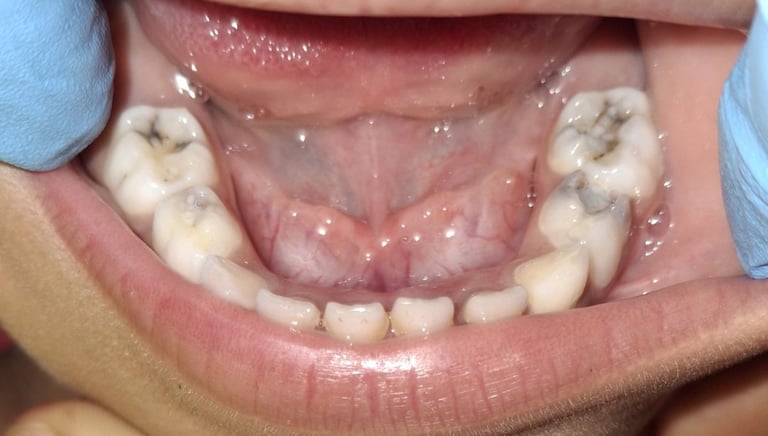

Clinical pictures of teeth requiring RCT

All images are of real cases of teeth where Root canal treatment was performed to remove infection and preserve the natural tooth restoring normal chewing and function of teeth.